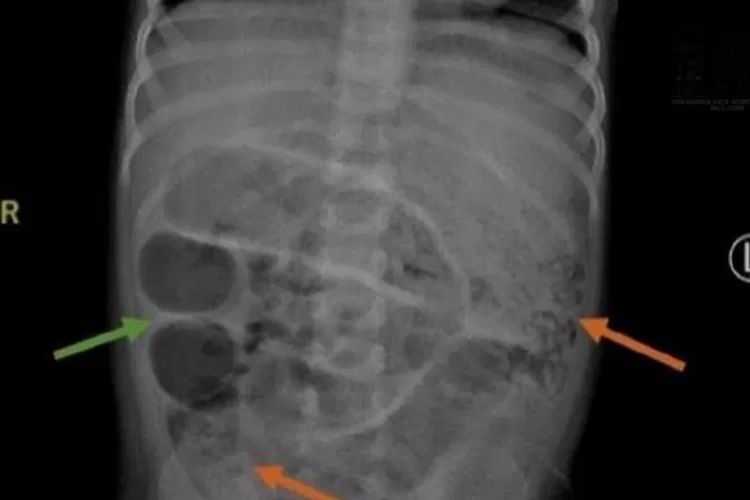

Seorang bocah laki-laki berusia 3 tahun harus menjalani operasi darurat karena ususnya dipenuhi oleh cacing gelang (ascaris lumbricoides).

Sang anak datang ke rumah sakit dengan perut membesar dan keluhan tidak bisa buang air besar selama seminggu.

Setelah dilakukan pemeriksaan, dokter menemukan infestasi cacing dalam jumlah besar di dalam saluran pencernaan.